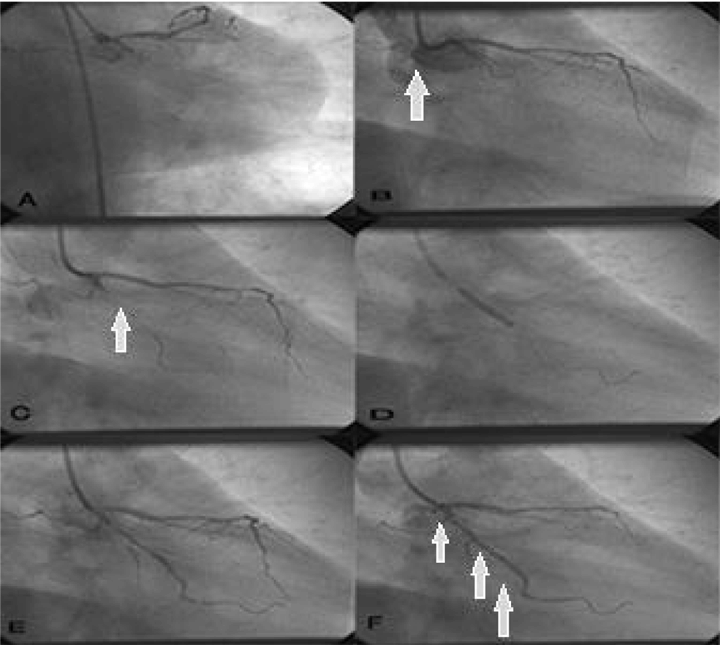

A 54-year-old male, known to have bronchial asthma (mild) well controlled with albuterol inhaler, was brought by his family to our emergency medicine department three hours after the onset of pressure like chest pain, which was central and radiated to the left arm. The patient reported taking an oral dose of amphetamine about seven hours before the presentation. The patient told that the chest pain was neither decreased nor increased by anything. The pain was associated with shortness of breath, nausea and vomiting. The patient had no history of palpitation, cough, wheezing, abdominal pain or back pain. He had no history of similar symptoms before, such as ischemic heart disease, diabetes mellitus, hypertension, hyperlipidemia, or atrial fibrillation. He had no family history of similar symptoms or coronary artery disease. He was not on any medication. He was not allergic to anything. He smoked one pack of cigarettes per day over the last 10 years. He used amphetamine tablets occasionally and had no history of drinking alcohol. At the time of arrival to the hospital, his blood pressure was 137/94 mmHg, heart rate was 77 beat per minute, respiratory rate was 17 breaths per minute, oral temperature was 37.2°C and oxygen saturation was 99% on room air. Generally, he appeared in severe respiratory distress, but alert and oriented. Cardiovascular examination revealed first and second heart sounds were within normal limits, point of maximum impulse was not displaced, and no rub, murmur or gallop sounds were exhibited. His lungs were clear to auscultation bilaterally. A 12-lead electrocardiogram showed a regular sinus rhythm (79/min) and T-wave inverted in lead I, aVL, (V4-V6). The patient had no previous ECG, echo, stress, or lipid profile reports for comparison Because of his lack of prior related symptoms. Laboratory data showed total creatine kinase (CK) level 1759 IU/L, CK-MB level 87U/L, and troponin-I level 13.38 ng/mL, a urine toxic screening test was positive for amphetamine. Based on the history, physical examinations and investigations, the diagnosis of non-ST elevation myocardial infarction (NSTEMI) was made. The patient was given aspirin 324 mg chew, clopidogrel 300 mg per oral, morphine sulfate 2 mg IV every 10 minutes as needed, subcutaneous low molecular weight heparin 60 mg (1 mg/kg) every 12 hours, and nitroglycerin infusion (10 to 20 µg/min). The patient began to experience a worsening angina pain and was not responding to treatment. However, there were no ECG changes from previous tests. The cardiologist decided to do percutaneous coronary intervention (PCI) with approximately 11 hours spanning from the presentation to emergency room visit. Coronary arteriography revealed a 100% stenosis in the proximal portion with large clot burden at LCX coronary artery. Finally, stent inflation was used with excellent results. He was discharged from the hospital after one week with orders to take baby aspirin per oral once a day and clopidogrel 75 mg per oral once a day for six months. Additionally, his medications for bronchial asthma were maintained and he was given an appointment for the cardiac clinic after one week. At follow-up, his blood pressure, lipid profile, and fasting blood sugar were within the normal range. | ||||||